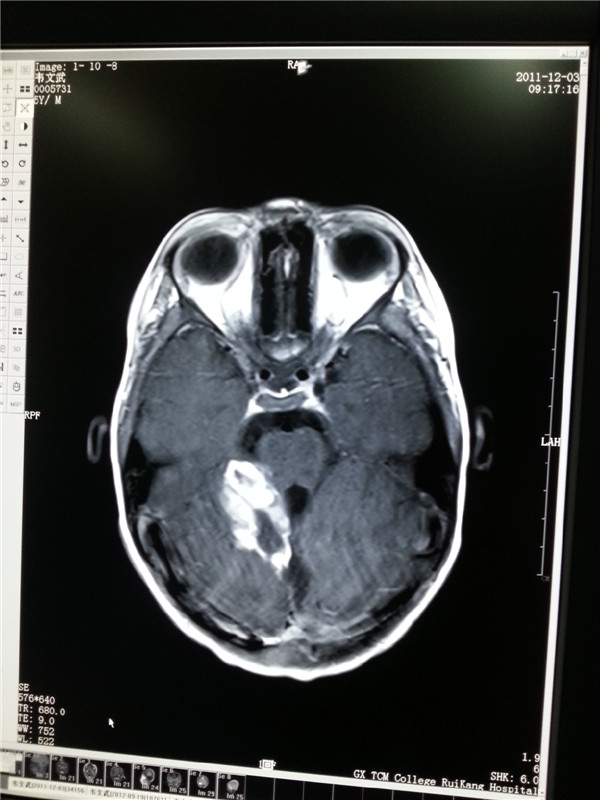

8岁的文文今年上小学二年级了,谁也想不到活泼好动的他,在三年前被检查出患有脑胶质瘤。日前,文文在父母的带领下来院复查。磁共振结果显示胶...